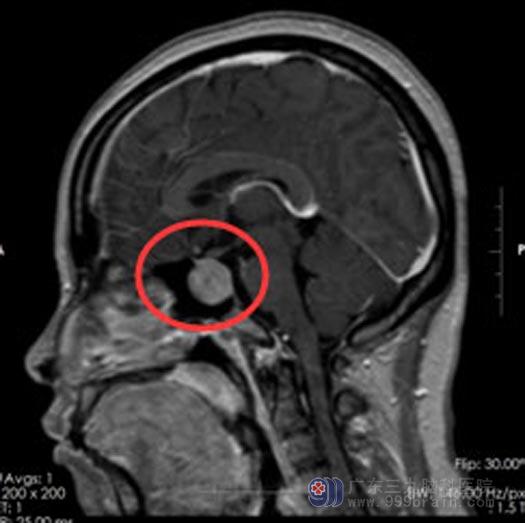

经家属同意后在内镜下经鼻碟鞍区行垂体腺瘤切除术,肿瘤顺利切除,术中对垂体、视神经、鞍底保护良好。术后无脑脊液漏、电解质紊乱等并发症,术后视力较前明显改善,泌乳素水平也渐渐恢复到正常范围。

手术前